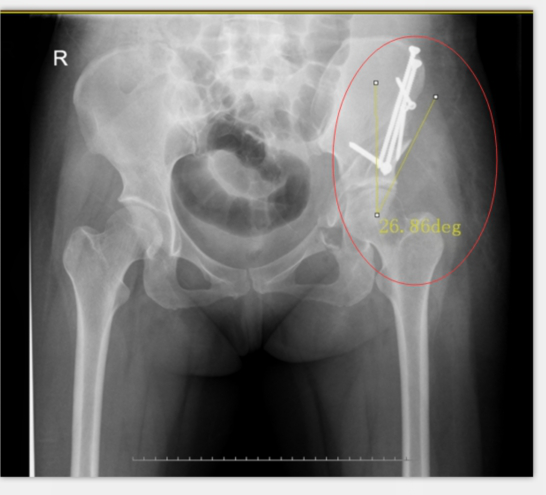

術(shù)中,左側(cè)髖臼周圍截骨

在李彬主任的帶領(lǐng)下,肖女士進行了髖臼周圍截骨術(shù)PAO保髖治療:調(diào)整髖臼位置,使髖關(guān)節(jié)的旋轉(zhuǎn)中心適度內(nèi)移;增加髖臼對股骨頭的覆蓋,增加負重的關(guān)節(jié)面,降低了髖關(guān)節(jié)負重面軟骨的應(yīng)力,達到了延遲或阻斷髖關(guān)節(jié)炎進展的目的,延長了自身髖關(guān)節(jié)的使用壽命。目前,患者恢復(fù)良好。

術(shù)后X光:CE角約26度,髖臼尺度正常